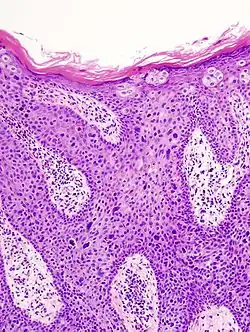

In situ disease

Bowen's disease is essentially equivalent to and used interchangeably with cSCC in situ, when not having invaded through the basement membrane.[12] Depending on source, it is classified as precancerous[13] or cSCC in situ (technically cancerous but non-invasive).[48][49] In cSCC in situ (Bowen's disease), atypical squamous cells proliferate through the whole thickness of the epidermis.[12] The entire tumor is confined to the epidermis and does not invade into the dermis.[12] The cells are often highly atypical under the microscope, and may look more unusual than the cells of some invasive squamous-cell carcinomas.[12]

cSCC in situ, high magnification, demonstrating an intact basement membrane.[12] -